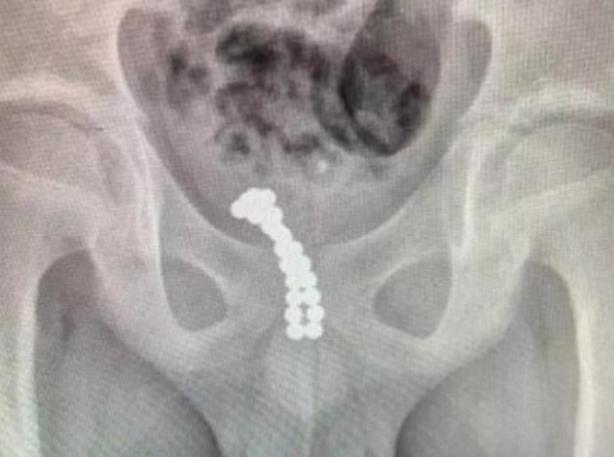

有一天妈妈在给宝贝收拾贴身衣物时,却发现上面有很多分泌物,味道非常大,母亲很生气,以为依依做了什么不应该做的事情。这时女儿才说之前会把面巾纸塞入*体下**,觉得很好玩,而且每次都可以扯出来,但上一次这么做的时候,有一半留在了身体内,没想到现在变得这样严重。

最重要的是依依并不是某个特殊的个例,这种事情在生活当中相对常见,之前广东省就有一个幼儿园的小朋友把异物放入*体下**。